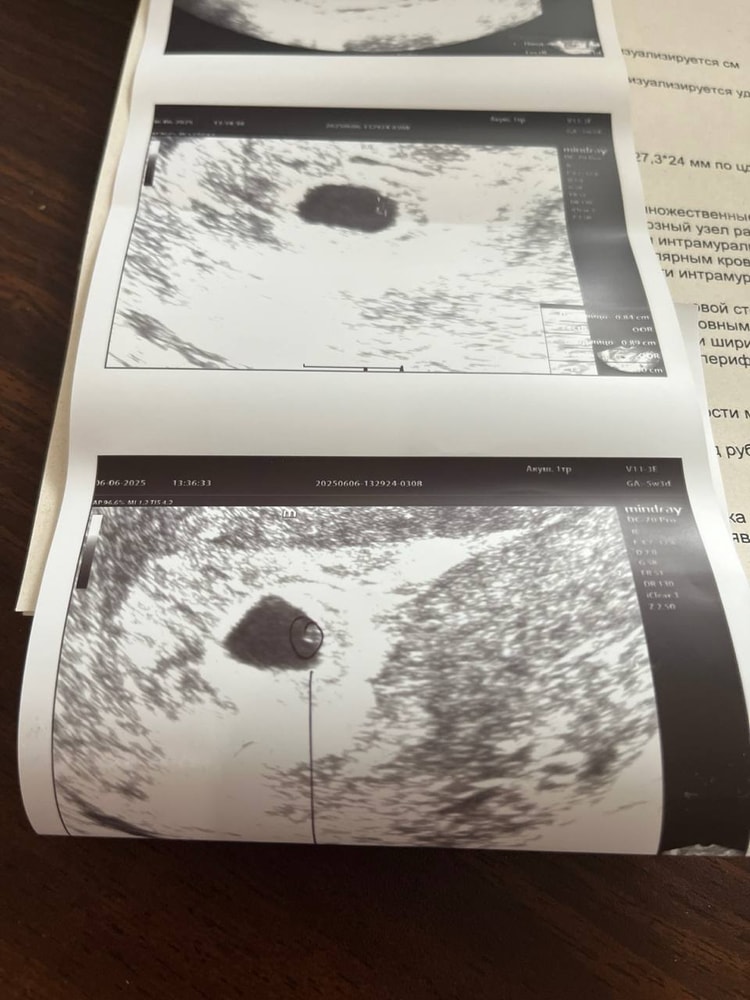

Затрудняюсь с категориейОх ,девочки! Сходила на узи 😭 по итогу пя выросло но не так как должно бы было вырасти … ЖМ нашли с трудом и он очень маленький 😭😭😭 сказали придти во вторник, если положительной динамики нет, то делать МА, типо до 42 дней по рекомендациям 😭😭😭

ЖМ 1 мм

пя 10,2